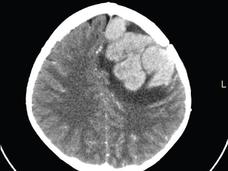

Children with Acute Lymphoblastic Leukemia Can Skip Radiation to the Brain

Only 1.5% of children with acute lymphoblastic leukemia who skipped radiation had a recurrence in the central nervous system, according to a recent trial. The therapy, which is intended to prevent such a recurrence, can have devastating side effects.